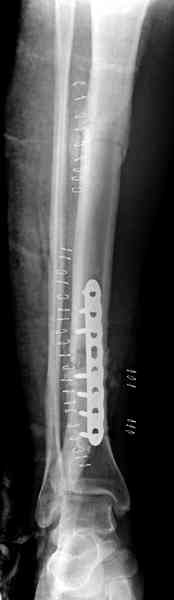

Не оригинальное, подход не раз был демонстрирован нас в стране проф. Анатолием Федоровичем Лазаревым (ЦИТО), который это называет "металлокаркасная пластика". У нас в институте в другом отделении он

помогал сделать несколько таких металлокаркасов, только, насколько я помню, без блокируемых стержней. А в мире эта методика довольно давно

применяется, хотя и не массово. Например, осенью прошлого года на конференции общества Кюнчера в Страсбурге было хорошее сообщение на эту тему. 17 больных, результаты уже до 5 лет.

The cages are commercially available but up to 10 cm. So we measured the needed length on x-rays, added 2 cm at both ends for sure that

the resected piece will include all, and resulted with 15 cm which one was ordered and individually made by the same factory. So yes, we made the gap to fit the cage.

The inner diameter of the tube is 13 mm, the nail was 12 mm, so not so much space to put something inside. Yes, this is really shaft endoprosthesis which i hardly ever would offer for a young football player. Though... Maybe we would when we collect some experience with this sort of implants to feel/prognose its strength in different settings.